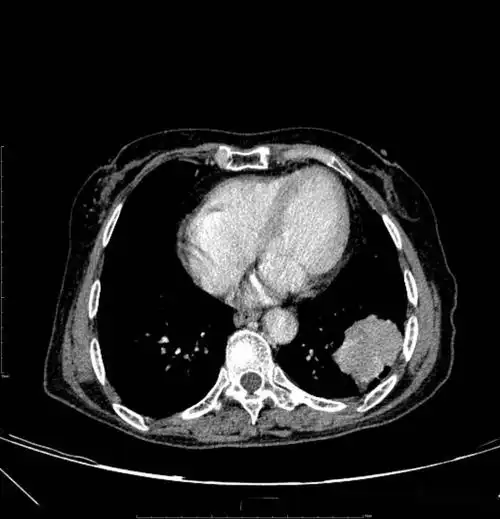

胸部ct平扫示左下肺占位肺癌

早期肺癌与晚期肺癌的ct影像